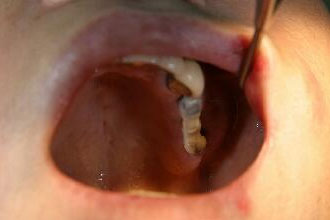

術前の口腔内写真

・骨が薄いので埋入手術後3本のインプラント体をスーパーボンドで固定

・再結晶化HAコーティング施されたインプラントフィクスチャーを使用したため自家骨の移植や人工骨の添加を行わないで直接埋入